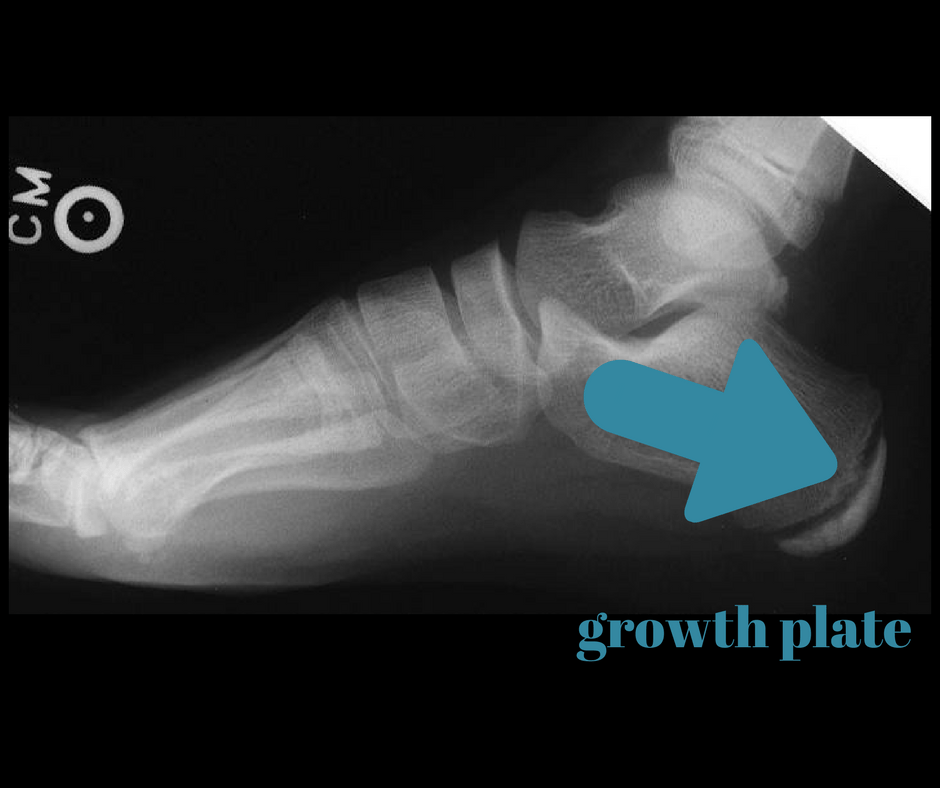

From slideplayer.com

Triage of Playground (and sports) injuries ppt download Baseball Cleats For Sever's Disease What is the treatment for sever's disease? Below i have listed what i believe to be the best baseball cleats for a player with sever’s disease: Rubber heel cups should be worn in all of your child’s shoes, especially in cleats. Sever’s disease (also known as calcaneal apophysitis) is one of the most common causes of heel pain in growing. Baseball Cleats For Sever's Disease.